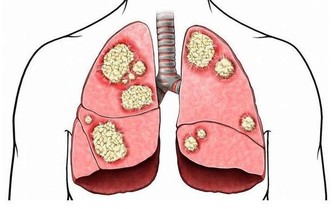

德國一個研究所對此展開了研究,結果發現缺硒會使肝癌的發病率提高10 倍。

該研究團隊大約蒐集了約48 萬名成年人的健康數據,進行了為期10 年的跟踪調查;

經統計,這些調查對像中包括121 名肝癌患者、100 名膽囊癌患者,以及40 名肝內膽管癌患者。

研究人員檢測了癌症患者的血硒水平,並與健康個體的血液樣本進行對比;

而後發現這肝癌患者的血硒水平都遠低於健康人。

與血硒水平較高的人相比,缺硒的個體罹患肝癌的風險要高出5 到10 倍。

不過該研究負責人表示,雖然目前確定了缺硒是誘發肝癌的主要因素之一,

但尚不能證明缺硒是否會增加膽囊癌和膽管癌的發病率。